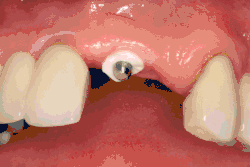

Single tooth implant restoration

Single tooth restorations are individual freestanding units not connected to other teeth or implants, used to replace missing individual teeth.[23] For individual tooth replacement, an implant abutment is first secured to the implant with an abutment screw. A crown (the dental prosthesis) is then connected to the abutment with dental cement, a small screw, or fused with the abutment as one piece during fabrication.[28]: 211–232 Dental implants, in the same way, can also be used to retain a multiple tooth dental prosthesis either in the form of a fixed bridge or removable dentures.

Single teeth, bridges and fixed dentures

An abutment is selected depending on the application. In many single crown and fixed partial denture scenarios (bridgework), custom abutments are used. An impression of the top of the implant is made with the adjacent teeth and gingiva. A dental lab then simultaneously fabricates an abutment and crown. The abutment is seated on the implant, a screw passes through the abutment to secure it to an internal thread on the implant (lag-screw). There are variations on this, such as when the abutment and implant body are one piece or when a stock (prefabricated) abutment is used. Custom abutments can be made by hand, as a cast metal piece or custom milled from metal or zirconia, all of which have similar success rates.[50]: 1233